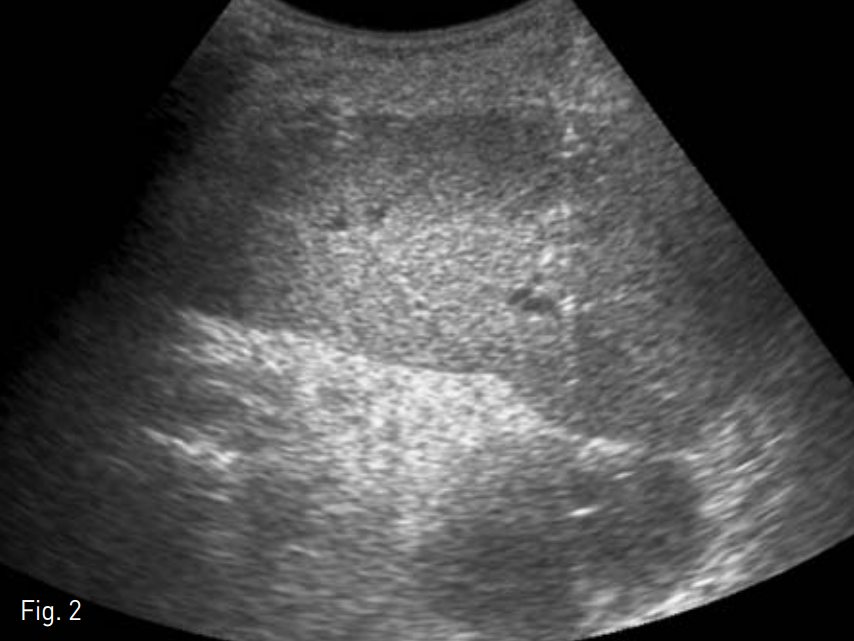

리도카인으로 국소마취를 시행한 후 초음파 유도 하에 비장문에 위치한 농양을 비장을 겅유하이 18G Chiba needle로 천자하였다(Fig. 2). 0.035-inch 유도철사(Terumo, Tokyo, Japan)을 삽입한 뒤 이를 따라 8.5-Fr pigtail catheter(Cook, Bloomington, IN, USA)를 삽입하여(Fig. 3) 40cc의 고름을 배액 하였다.

Fig. 3

Final fluoroscopic image shows adequate placement of drainage catheter within the contrast filled abscess cavity.